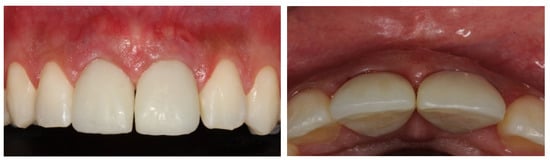

Result and Follow-Up